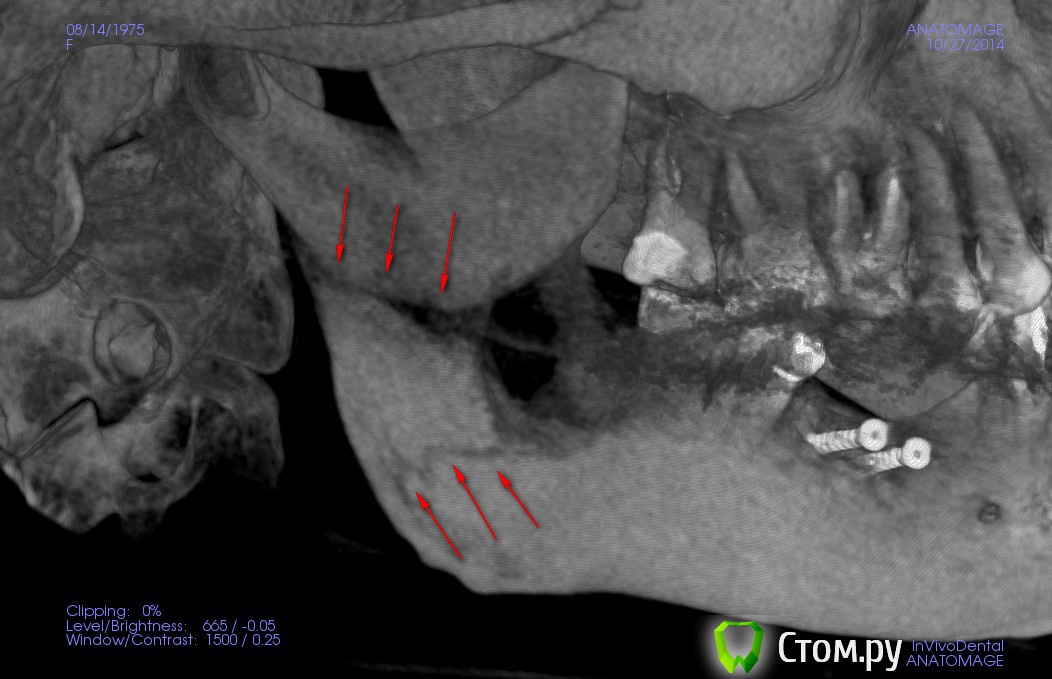

kriokov Опубликовано 23 ноября, 2014 Поделиться Опубликовано 23 ноября, 2014 Хорошо, вот: Марьяна Александровна, по панораме.Мне кажется нет перелома нижней челюсти в обл угла и в обл ветви. Но это мое личное мнение и я его попытаюсь обосновать.Зеленая стрелка показывает на место забора блокажелтая на линию восходящей части венечного отростка-- там нет непрерывностисиняя стрелка -- ветвь, линия может быть и артефактом связанным с забором блока, если он был значительным по протяжению.Мне кажется , Вам надо списываться с доктором, ( напомнить ему , что Вы стоматолог, еще раз без обиняков изложить все вопросы которые Вас тревожат), осмотр, и решать , что дальше делать. http://www.imageup.ru/img214/1954483/maryana.jpg Ссылка на комментарий

Марьяна Опубликовано 23 ноября, 2014 Автор Поделиться Опубликовано 23 ноября, 2014 (изменено) Если и был перелом, то без смещения и уже зажил...отправьте дайкомы Дмитрию Рогацкину.Да, зажил, и слава Богу. Отправлять дайкомы Рогацкину смысла нет. Он скажет, то, что есть. А есть двойной перелом. Я сама есть консультант по 3D КТ, :-) С Иваном Морозовым , который представляет Рогацкина у нас в Новосибе мы уже пообщались и в Анатомаже он и сделал мне одну из нарезок. И рентгенолог, которго хвалит Рогацкин, тоже в курсе)Смещение , кстати, есть, небольшое, дистально.Это видно по дистальному контуру ветви.Почему я выношу на общее обсуждение свою историю? Ну мне обидно, да. Обидно, что со мной так обошлись коллеги. Что по необъективным причинам, без уведомления был изменен план лечения. Что скрыли истинную причину, по которой срочно прекратили операцию и отложили вторую на две недели. Позиция лечащего врача сейчас убивает наповал. Я даже по-началу засомневалась в своей компетентности, увидев повторное КТ и его резюме по нему.Я ещё хотела написать вот что. Суть моего поста здесь. По факту..я имею право предьявить претензию, но не хочу. Слава Богу, что все обошлось без серьезных осложнений. Что не было остеомиелита, что не случилось явного смещения, несмотря на то, что перелом не был шинирован и т.д. и .т.п.Я оскорблена поведением врача. У нас у всех есть свое маленькое кладбище и мы знаем и помним о всех своих ошибках. Но надо уметь признавать ошибки и исправлять. И если именитый врач ведет себя, как нашкодивший пацан...если между коллегами такое вот отношение, страшно за пациентов, которые вообще не в теме.В общем...лозунг какой-то получился) Уважайте своих пациентов и друг друга. Изменено 23 ноября, 2014 пользователем Марьяна 5 Ссылка на комментарий